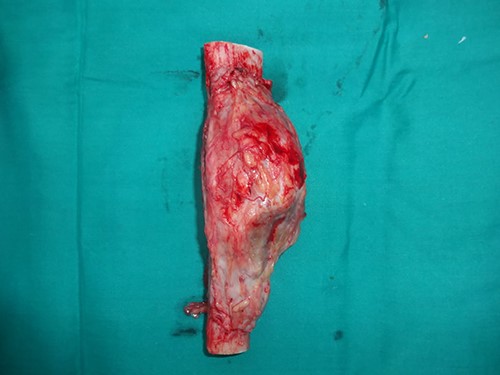

A 33-year-old gentleman presented with slow-growing swelling over the anteromedial aspect of the midshaft of left leg with dull aching pain for 2 years. The swelling was bony hard, 10 cm long and was fixed to the underlying tibia (Fig. 1). Anterior and posterior tibial arteries, sensory and motor functions of the affected legs were intact. Preoperative incisional biopsy report shows multiple epithelial-like cells in a background of fibrous dysplasia, suggestive of adamantinoma. X-ray suggested lytic expansile lesion with multiple septa and sclerotic margins involving the tibia’s diaphysis (Fig. 2). Computed tomography scan showed a cystic expansile lesion with a sclerotic margin obliterating the medullary cavity. Chest X-ray and abdominal ultrasound were normal. The bony defect in the tibia after wide excision of the tumour was 16 cm (Fig. 3) reconstructed with free fibula flap harvested from the opposite leg (Fig. 4). The bone flap was fixed to the tibia with a dynamic compression plate and bicortical screws (Fig. 4). The fibula flap pedicle, peroneal artery and one venae comitantes were anastomosed with the posterior tibial artery and great saphenous vein, respectively. Post-operatively, the flap, flap donor site and recipient’s leg wound healed without complications. Histopathological examination of excised lesion confirmed the diagnosis of classic adamantinoma with margins free of tumour (Fig. 5). After 1 year, there was radiological bone union, evidenced by uninterrupted bony borders between the fibula and recipient tibia bone, obscured osteotomy line at both the junctions and hypertrophy of the transferred fibula as per the bone union criteria by Hsu et al. [3]. The patient started partial weight-bearing in the operated limb after 6 months without any displacement or fracture of the vascularized bone graft. Three years post-surgery follow-up showed good evidence of bony integration and hypertrophy of the bone of the fibula flap, gradually accepting the shape of the tibia without any local recurrence or distant metastasis (Fig. 6). Patient is completely bearing weight on the affected lower limb with good function (Fig. 7).